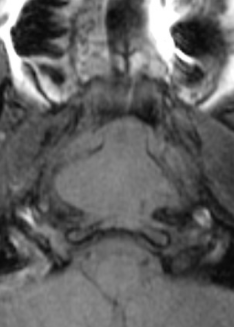

Chordome du Clivus

- Tumeur de reliquat embryonnaire de reliquat du notochorde ( qui donne les corps vertébraux )

- Localement agressive

- Se trouvent sur tout le squelette axial mais Sacro-Coccygien et Base du Crane ++

- Très hyperT2 avec prise de contraste

- Destruction osseuse alentour

chrodome